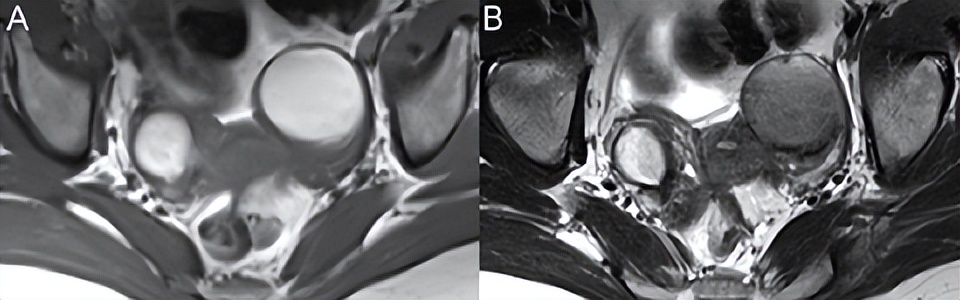

在T1WI上呈高信号的子宫内膜异位囊肿出现在图76.4A的轴位T1WI的两侧。更具体的表现是T2WI上的(B)左侧病变,表现为“阴影征”,可视为信号强度完全丧失。纤维瘤谱肿瘤(纤维瘤、卵泡膜细胞瘤和纤维卵泡膜细胞瘤)的低信号是良性特有的。在Meigs综合征中,此类病变可能与腹水和胸腔积液相关。延迟增强很常见。大病变中的水肿会在T2WI上增加信号,而脂肪含量随着病变中卵泡膜细胞成分的增加而增加。

▲ 图76.4